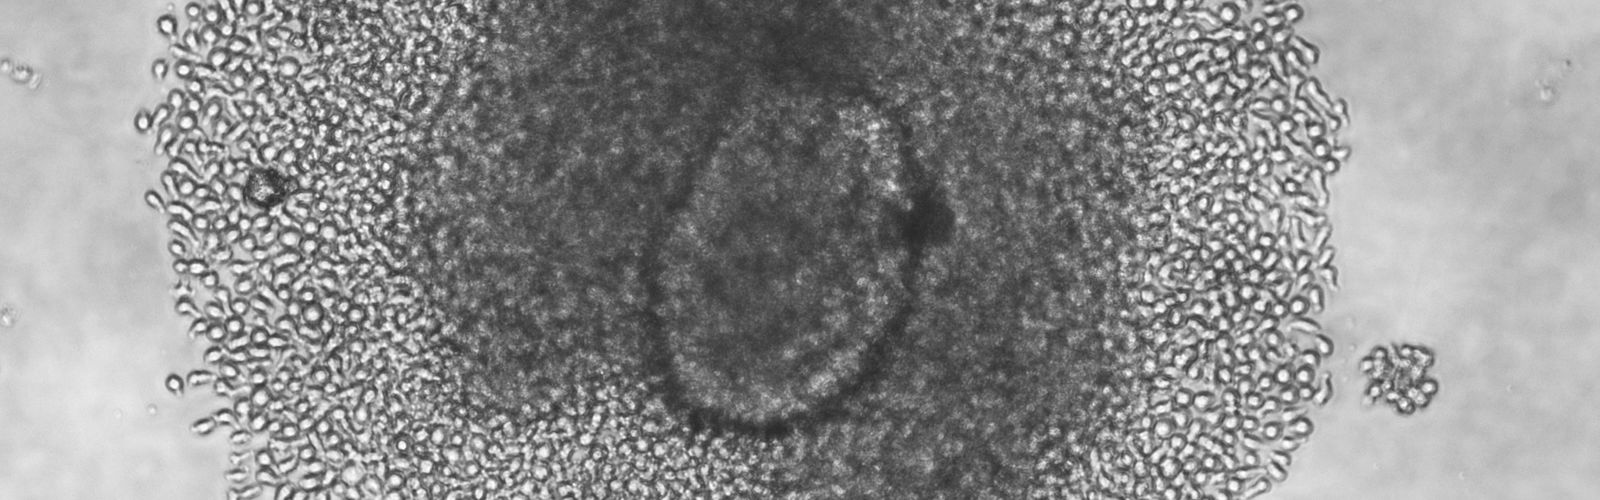

In a highly collaborative effort, scientists at UMass Chan Medical School have isolated and characterized a large bank of live islet-infiltrating T cells directly from the islets of tissue donors with type 1 diabetes. The findings, published in Nature Medicine, have direct implications for the design of therapies and preventative strategies for those with type 1 diabetes and those at risk for developing it.

Using live islets from nine type 1 diabetic donors, Kent Lab sorted live lymphocytes by fluorescence activated cell sorting. They also used an improved tissue culture method they developed to grow lymphocytes from the islets. 236 T cell lines were derived from the islets, and they analyzed the function of 50 lines, discovering the specific reactivities of 18 lines. LEARN MORE